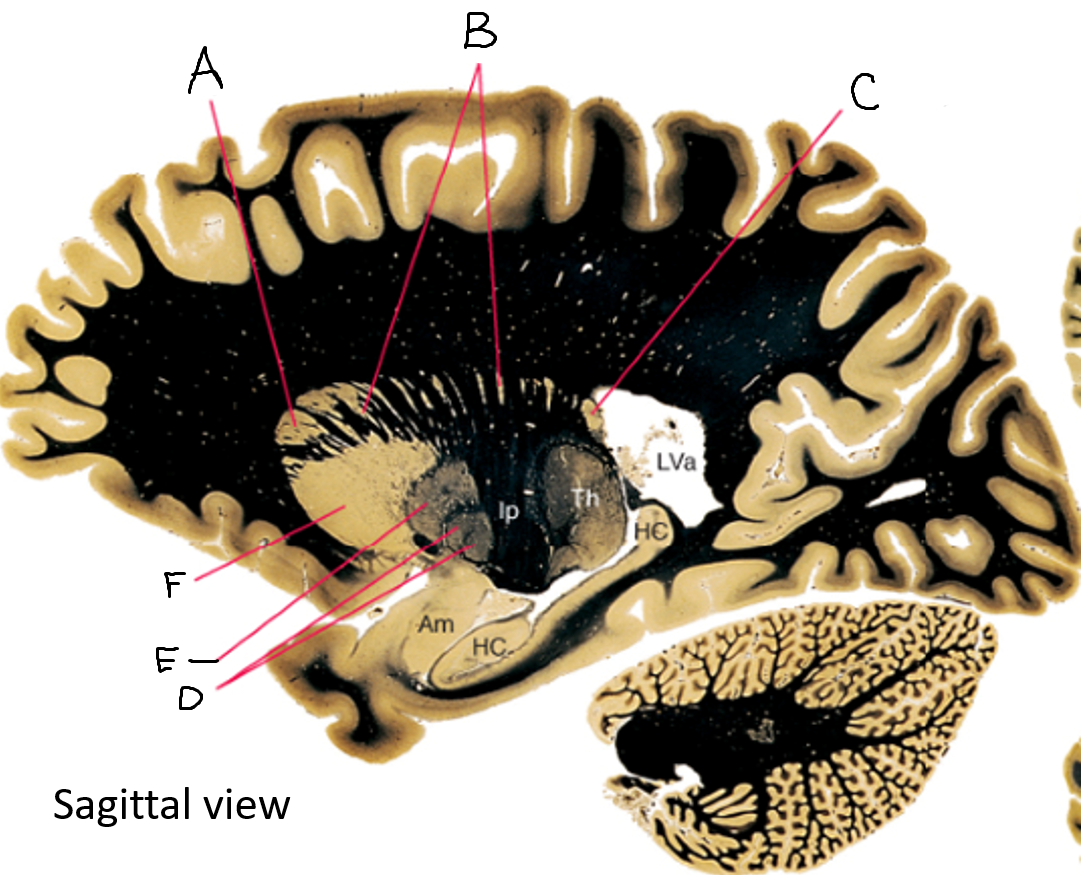

A

head of caudate nucleus

C

putamen

D

external segment of globus pallidus

E

internal segment of globus pallidus

F

third ventricle

G

thalamus